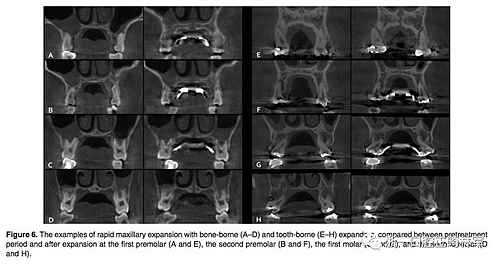

(1)牙支持式和骨支持式快擴之間的比較(Figure 6,Table 1)

骨骼變化:腭中縫線在兩組中都以三角形模式被成功打開,鼻底增加最少,硬腭以下5mm平面出被打開最多(P<0.001)。骨骼的擴張比牙齒的水平要少。除了第一前磨牙區(qū)域的線性測量值外,骨支持式組顯示擴張程度比牙支持式組顯著增加。

牙性變化:兩組的牙槽骨和牙長軸的角度變化都很明顯。牙支持式組在全部區(qū)域都顯示出比骨支持式組更大的頰側傾斜(P<0.01)。牙支持式組的牙槽骨頰傾更明顯,第二磨牙區(qū)域除外(P <0.05)。在第一前磨牙和第一磨牙,兩組在根尖處的橫向距離增加是相似的。然而,在第二前磨牙和第二磨牙中,牙支持式組發(fā)生根尖橫向距離增加較少。在牙冠水平,僅在第二前磨牙處,兩組之間的擴張相似。牙支持式組在第一前磨牙和第一磨牙產(chǎn)生更多的牙冠之間橫向距離增加,而骨支持式更多發(fā)生在第二磨牙。在第一前磨牙和第一磨牙的垂直向變化方面,兩組之間沒有區(qū)別。 第二前磨牙區(qū)頰尖頰傾和腭尖掛下在牙支持式組比骨支持式組更明顯(P <0.05)。在第二磨牙區(qū)域,僅在頰尖頰傾方面兩組有統(tǒng)計學差異(P <0.05)。除了第一前磨牙在牙支持式組的頰側骨開裂明顯(P <0.01)之外,兩組間垂直牙槽骨損失量沒有顯著差異。